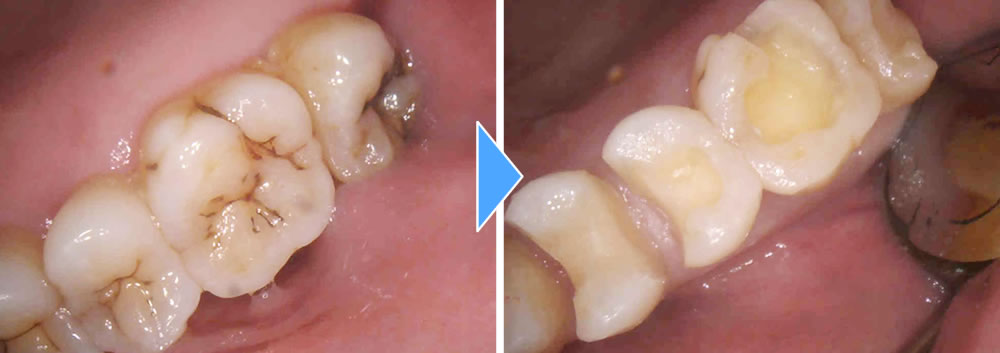

むし歯治療